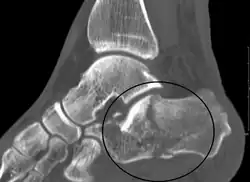

Conventional radiography is usually the initial assessment tool when a calcaneal fracture is suspected. Recommended x-ray views are (a) axial, (b) anteroposterior, (c) oblique and (d) views with dorsiflexion and internal rotation of the foot. However, conventional radiography is limited for visualization of calcaneal anatomy, especially at the subtalar joint. A CT scan is currently the imaging study of choice for evaluating calcaneal injury and has substituted conventional radiography in the classification of calcaneal fractures.[13] Axial and coronal views are obtained for proper visualization of the calcaneus, subtalar, calcaneocuboid and talonavicular joints.

Calcaneal fractures are categorized as intra-articular or extra-articular on the basis of subtalar joint involvement. Intra-articular fractures are more common and involve the posterior talar articular facet of the calcaneus. The Sanders classification groups these fractures into four types based on the location of the fracture at the posterior articular surface. Extra-articular fractures are less common and may be located anywhere outside the subtalar joint.[13] Extra-articular fractures are categorized depending on whether the involvement of the calcaneus is anterior (Type A), middle (Type B) or posterior (Type C).[15]

The Angle of Gissane, or "Critical Angle", is the angle formed by the downward and upward slopes of the calcaneal superior surface. On a lateral radiograph, an angle of Gissane > 130° suggests fracture of the posterior subtalar joint surface. Böhler's angle, or the "Tuber Angle", is another normal anatomic landmark seen in lateral radiographs. It is formed by the intersection of 1) a line from the highest point of the posterior articular facet to the highest point of the posterior tuberosity, and 2) a line from the former to the highest point on the anterior articular facet. Böhler's angle is normally 25° to 40°.[14] It is named after Austrian physician Lorenz Böhler.[16] A decreased angle is indicative of a calcaneal fracture.